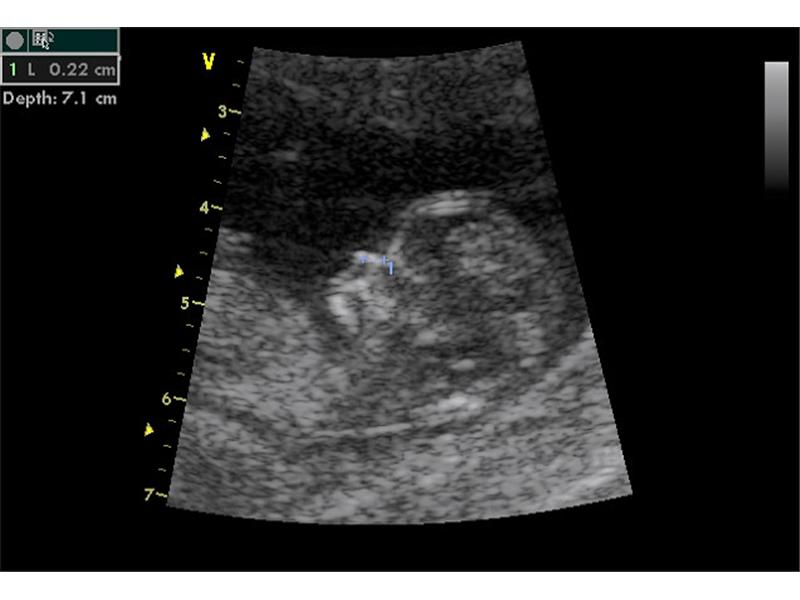

První fotečky

2 fotografií

Zdroj: archiv redakce